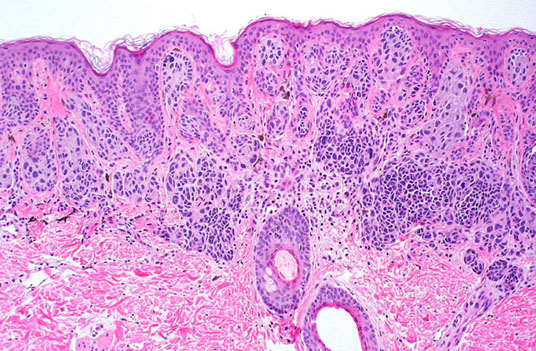

Bowen's disease

Micro: clonal atypical skin cells found throughout epidermis - a full thickness "wind-blown" appearance

- inc (atypical) mits, intercellular bridges, can go into sweat glands

IHC: (+) p53, HMWK (CK903), HPV

Genes: aneuploidy